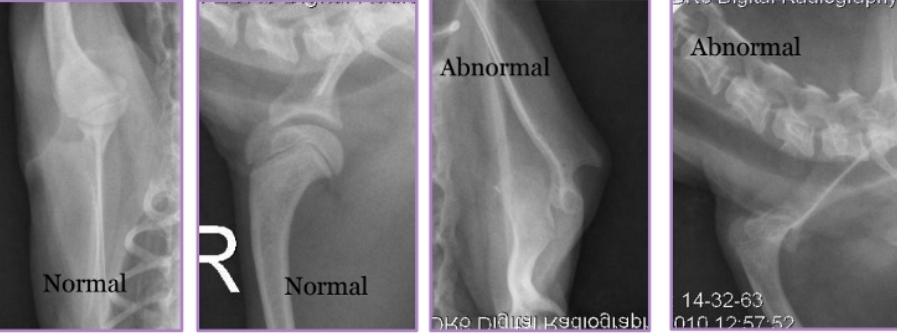

Ununited Anconeal Process

Et: Anconeal process of ulna fails to unite with proximal ulnar metaphysis

Failure of endochondral ossification, Joint incongruity

Hereditary, environmental, hormonal factors

Sig: Large breeds, GSD, Male > female, 5-12 months

Dt: Radiographs FLEXED lateral!

Osteophytes, Effusion, Anconeal process fragment, Joint incongruity

Tx:

Rx: OA management

End stage or financial issues

Sx: #1 , <1yr - early sx **

Early: primary repair, viable cartilage

Ulnar osteotomy → remove stress, allow fusion

Lag screw fixation of anconeal process

Chronic: excision of anconeal process

Elbow Incongruity

Et: Asynchronous growth of radius and ulna

Dt: radiographs

Tx: Corrective ulnar ostectomy (short radius syndrome)

Redistribute stress in joint

Allow bone alignment at joint level

Decrease joint stress